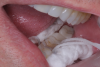

A 56-year-old female patient required an extensive treatment plan, including multiple crowns and fillings in each quadrant. She was able to complete treatment only in stages. By the time one quadrant was completed, she began to have pain on the mesial of tooth No. 20 (Figure 1 and Figure 2). Because the patient had no more dental benefits for the year, she needed to alleviate the sensitivity and prevent further problems between appointments. The doctor recommended SDF to stave off the sensitivity she was experiencing and to prevent growth of the lesion. Silver diamine fluoride was placed during a restorative appointment, and her sensitivity and pain subsided. When she returned a month later for her hygiene visit, she stated her pain had returned. A second SDF treatment was administered, which prevented the pain from returning a third time, until her restorative treatment could resume.

(1.) Patient exhbitied pain on the mesial of tooth No. 20.

Figure 1

(2.) Patient required an extensive treatment plan, including multiple crowns and fillings in each quadrant.

Figure 2